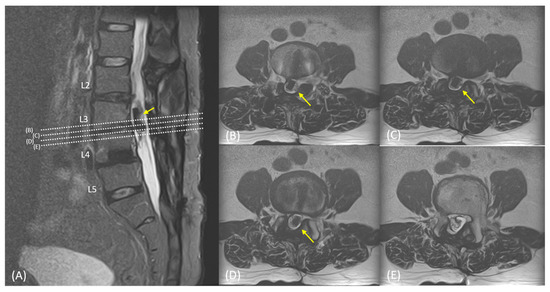

2. Case Presentation